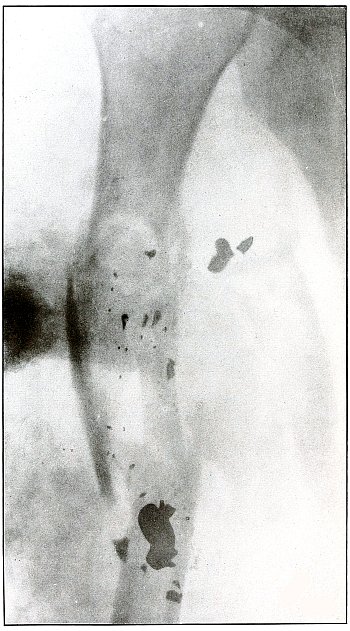

Plate 51.

[Pg 113]

Rifle—Plate 51.

LOWER EXTREMITY.

Gunshot Wound of the Thigh,

with Lodgment of the Missile.

As there is no injury to the bone, the bullet is not deformed. Its

penetrating power was not great enough to carry it through the tissue

so it must have struck the leg at extreme range when its energy was

almost spent.

The actual length of the bullet is 1.25 inches; the length of the

shadow is about 1.50 inches.

The increased length and the relatively slight density of the shadow

indicate the bullet to be some distance from the plate. The case

history places the wound in the right thigh, and the posterior surface

of the leg lay next to the photographic plate. As the density of the

shadow is not greater than the thickest portion of the bone, the

bullet probably lies in front of the border of the outer tuberosity of

the femur.

Although the surgeon’s diagnosis had to be made from the only

available plate, there is something of a speculative element in these

deductions, because if the reaction in the knee joint prevented the

patient from extending the leg the increased length of the bullet

shadow could be accounted for by this position, which would permit the

bullet to lie behind the bone and yet far enough from the plate to

account for the shadow enlargement. The nose of the bullet is at

the epiphyseal line, which is shown in the femur.